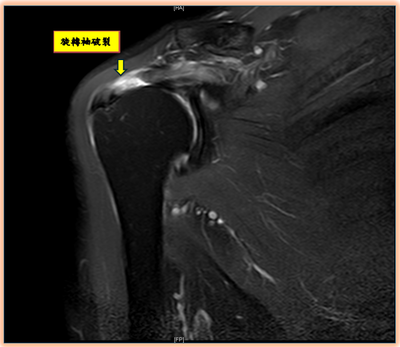

肩膀抬不起來?當心旋轉袖破裂

〈114年11月6日星期四〉【記者王可米/臺北報導】「最近連梳頭、穿衣服都舉不起手,還以為只是五十肩,結果檢查才知道是旋轉袖肌腱破裂。」一位六十多歲的小林女士(化名)就診時這樣描述。許多人誤以為肩膀疼痛或手...